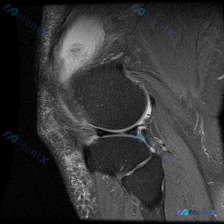

这是一张膝关节矢状位T2加权MRI图像,需要评估是否存在半月板异常,图像质量清晰,能看到股骨远端、胫骨近端、髌骨、髌下脂肪垫、关节间隙等全部关键结构。

- 半月板:内/外侧半月板的前角、体部、后角都是均匀低信号,形态完整,没有看到裂隙样高信号,没有明确的撕裂或者退变性异常征象

- 髌下脂肪垫:髌骨下方髌下脂肪垫区域可见广泛片状高信号,这是明确的水肿/炎症改变

- 关节腔:髌上囊和关节腔内可以看到中等量高信号液体影,提示存在关节积液

- 其他结构:股骨胫骨骨髓信号均匀,没有骨髓水肿或骨折;交叉韧带走行连续,信号正常;关节软骨面连续,间隙正常,没有看到明确异常